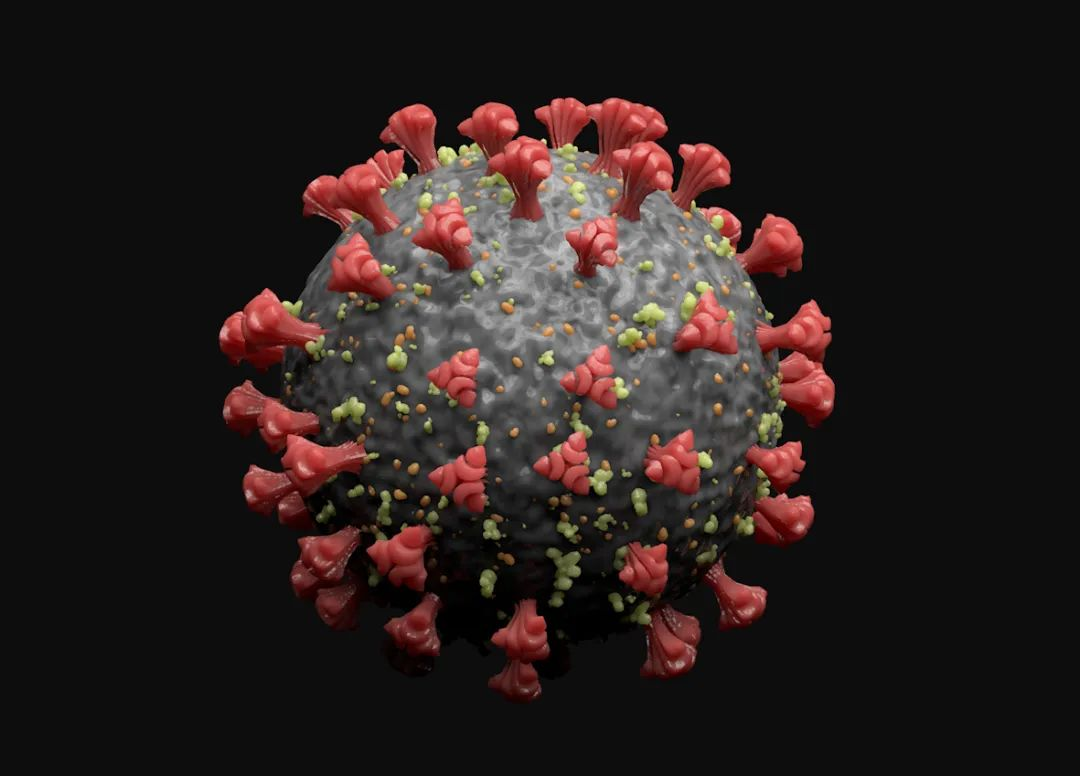

期刊封面图设计

滑动查看更多 点击查看大图